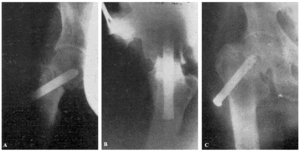

Fracaso número 2(observación número 2). F. S., setenta años4. Ingresa en el servicio con una fractura mediana del cuello femoral izquierdo. Osteosíntesis extraarticular (fig. 3. A y B). La impactación no ha resultado perfecta.

Figura 3. A: obs. núm. 2. El clavo no penetra suficientemente y la impactación, salvo en la parte superior de la línea de fractura, es muy defectuosa. B: obs. núm. 2. La posición del clavo es buena. C: obs. núm. 2. El clavo tiende a ser expulsado hacia fuera y apenas penetra en la cabeza femoral.

A los veinte días de la intervención pasa el enfermo a su domicilio, recomendándole que continúe en la cama. Pasado un mes vemos nuevamente al enfermo, el cual nos manifiesta que anda con mucha más dificultad que en los primeros días de permanecer en su domicilio, que fue cuando, por no haber interpretado bien nuestras indicaciones, comenzó a emprender la marcha. La radiografía (fig. 3. C) demuestra que el clavo apenas penetra en la cabeza femoral. A los ocho días hacemos otra radiografía (fig. 4. A), observándose que el trocáncer ha ascendido, a pesar de continuar guardando cama el enfermo. Ingresa nuevamente en el servicio, donde, con anestesia raquídea, retiramos el clavo, reduciendo las fracturas y volviendo a colocar un clavo más largo en buena dirección (fig. 4. B). Una radiografía practicada siete años y medio más tarde demuestra la no consolidación de la fractura, trastornos tróficos en cuello y cabeza femoral y que el cabo ha penetrado en el fondo de la cavidad cotiloidea, en donde ha labrado una cavidad (fig. 4. C).

Figura 4. A: obs. núm. 2. El trocánter ha ascendido francamente con relación a la radiografía anterior. El clavo tiende a salir de la cabeza por su parte superior. B: obs. núm. 2. Se extrajo el clavo y se colocó otro. El nuevo clavo está colocado en buena dirección, pero la reducción no es perfecta. C: obs. núm. 2. El clavo ha penetrado en el fondo de la cavidad cotiloidea, en cuyo lugar ha labrado una cavidad. Trastornos tróficos en cuello ycabeza femoral. El cuello del fémur ha desaparecido casi completamente.

En este caso el fracaso se debe a que la impactación no fue perfecta, y sobre todo, a haber el enfermo iniciado la deambulación al mes de intervenido, a pesar de que nosotros le ordenamos que guardara cama.